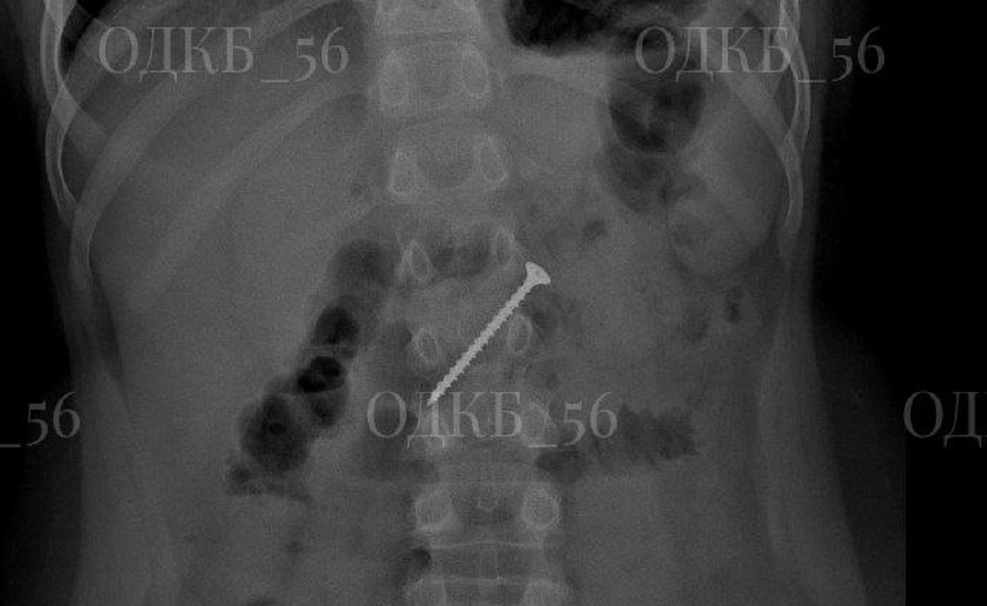

Родители заподозрили неладное и обратились к медикам. Рентген показал в желудке инородное тело. Ребёнка доставили в ОДКБ, где команда специалистов под общим наркозом выполнила эндоскопию. Саморез уже мигрировал в двенадцатиперстную кишку, создавая риск кишечной непроходимости и перфорации.

Благодаря профессионализму врачей операция прошла успешно.

Инородный предмет был удалён, ребёнок выписан домой в удовлетворительном состоянии.